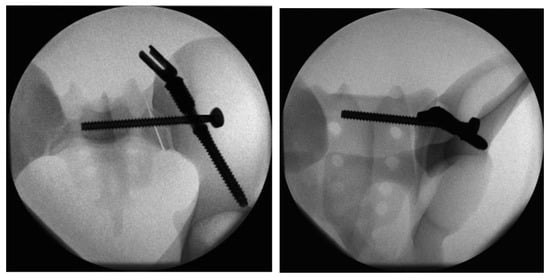

Figure 1.

Image of the triangular fixation system (TFS) configuration in Group I: a fenestrated iliac screw and an iliosacral screw with a premounted washer stabilize the dorsal pelvic ring. Lumbo-pelvic stabilization is achieved by connecting the polyaxial head adapter of the iliac screw to a pedicle screw rod system.